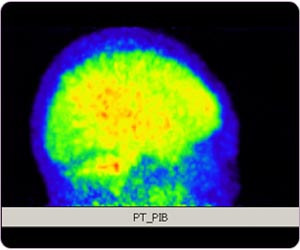

阿耳滋海默氏病 (11C标记PIB正电子扫描脑部)

11C标记PIB脑部正电子扫描:基於区域的定量分析